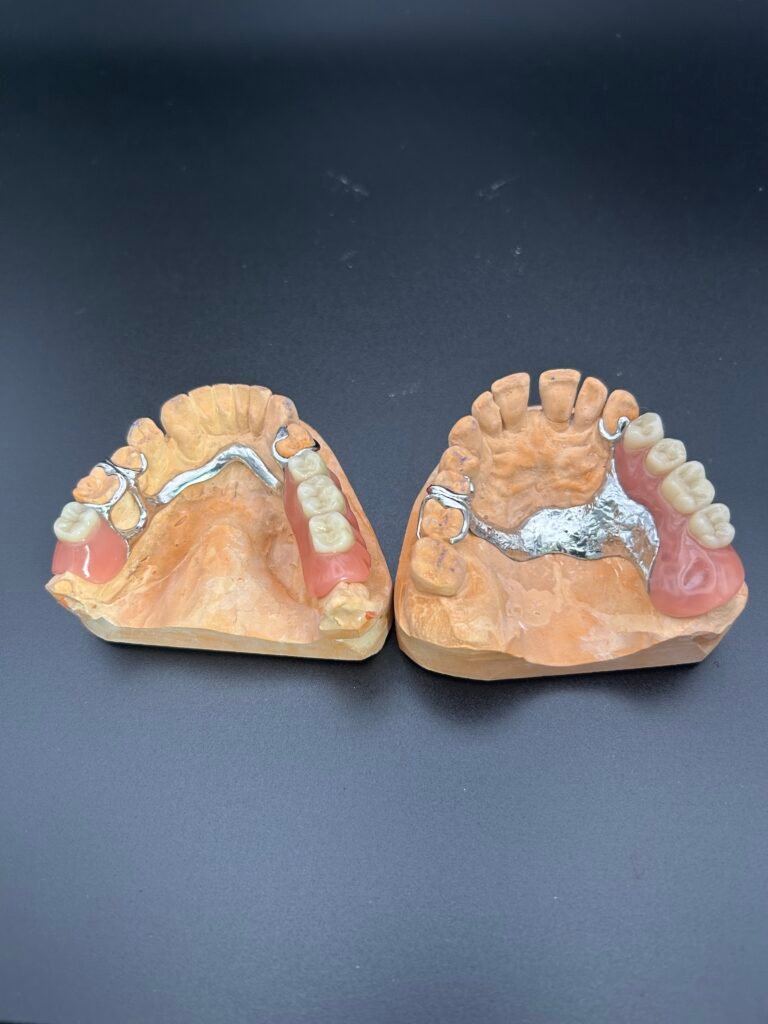

Auf dem Bild sehen Sie zwei Modellgussprothesen auf Arbeitsmodellen. Diese herausnehmbaren Teilprothesen bestehen aus einer stabilen Metallbasis und dienen der Versorgung von Lücken im Seitenzahnbereich. Die Prothesen zeigen typische Halteelemente.

Dank ihrer passgenauen Anfertigung bieten Modellgussprothesen eine funktionelle und langlebige Lösung bei teilweisem Zahnverlust. Bewährt, sicher und wirtschaftlich.